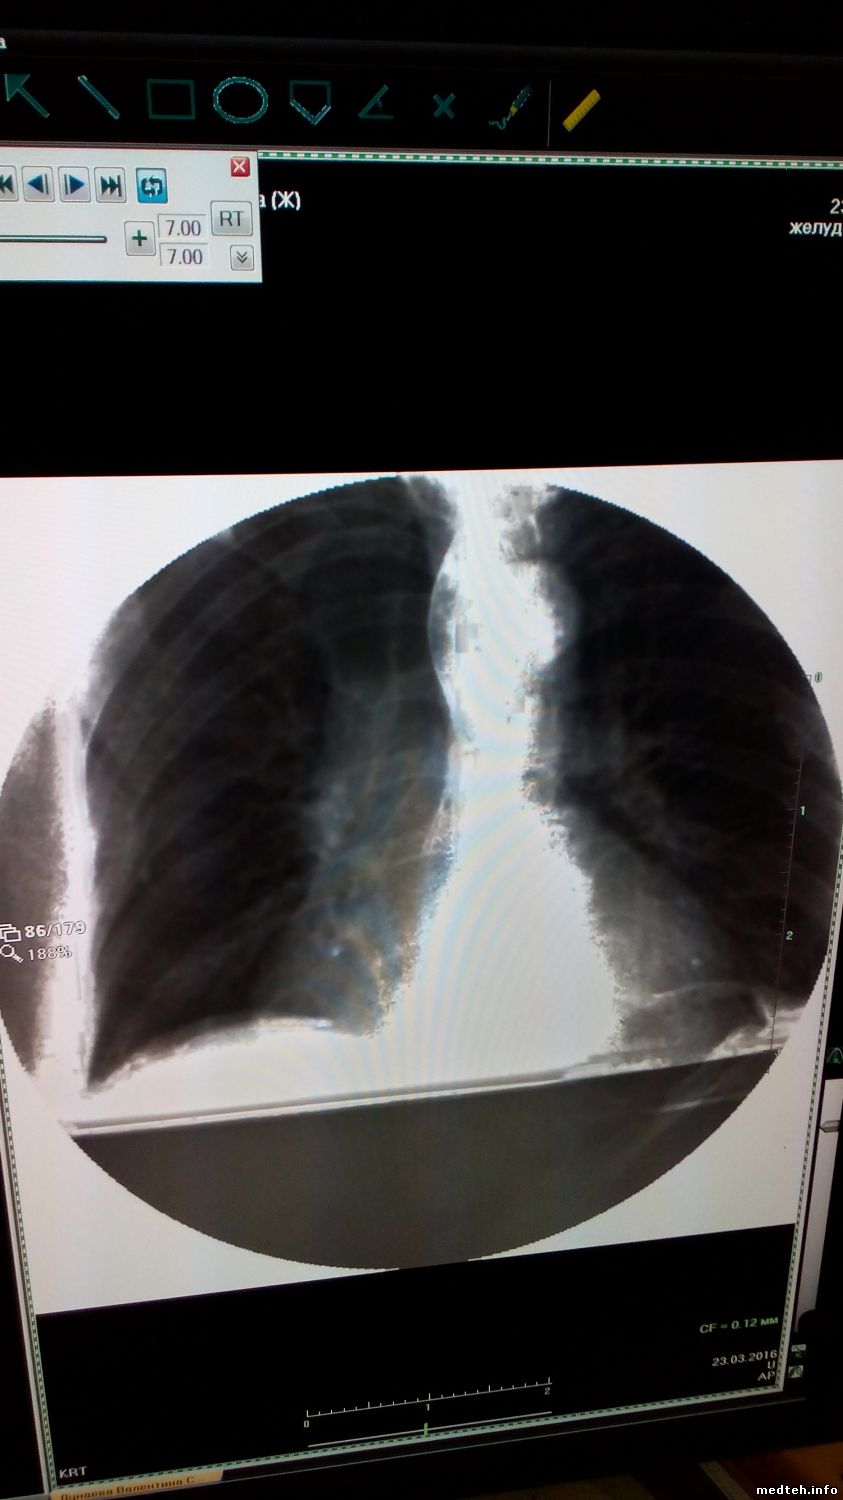

Всем добрый день, появилась проблема с КРТ Око, скопия ведет себя не стабильно (фото). При исследовании, изображение может пропасть, может быть искажено либо вообще отсутствовать.При этом аппарат не выдает никаких оошибок. С графией таких проблем нет, работает стабильно. Подскажите куда копать, насколько я понимаю, обработкой изображения занимается станция лаборанта. Спасибо.

0962386.jpg (116.6 Kb) · 7747136.jpg (76.0 Kb) · 3348363.jpg (86.6 Kb) · 4345735.jpg (135.3 Kb)